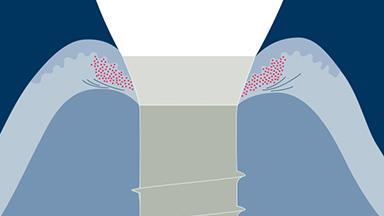

For a good long-term outcome of an implant-supported reconstruction, both hard and soft tissue need to be stable and to provide an adequate support for the prosthetic reconstruction.

There are various risk factors that may affect the success and survival rates. A clinician planning an implant therapy needs to know the risk factors that contribute to the different types of complications that can occur after implant treatment.